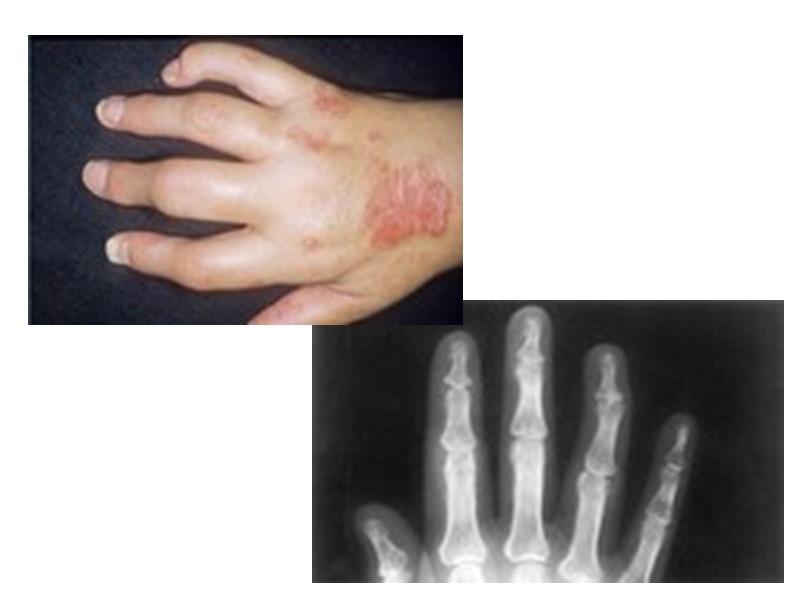

Рентгенологические признаки, помогающие отличить псориатический артрит от других воспалительных ревматических заболеваний суставов: Асимметричность поражения суставов кистей. Артрит на рентгенограммах может быть без околосуставного остеопороза. Изолированное поражение дистальных межфаланговых суставов кистей при отсутствии изменений или небольших изменениях в других мелких суставах кистей. Осевое поражение 3-х суставов одного пальца. Поперечное поражение суставов кистей одного уровня (одностороннее или двухстороннее). Деструкции концевых фаланг (акроостеолиз). Концевое сужение (атрофия) дистальных эпифизов фаланг пальцев рук и пястных костей.

Рентгенологические признаки, помогающие отличить псориатический артрит от других воспалительных ревматических заболеваний суставов (продолжение): Чашеобразная деформация проксимальной части фаланг пальцев кистей вместе с концевым сужением дистальных эпифизов - симптом «карандаш в колпачке» . Костные анкилозы, особенно проксимальных и дистальных межфаланговых суставов кистей. Множественный внутрисуставной остеолиз и деструкции эпифизов костей с разнонаправленными деформациями суставов (мутилирующий артрит). Воспалительные изменения в крестцово-подвздошных суставах -сакроилеиты (обычно двухсторонние асимметричные или односторонние; возможно отсутствие сакроилеита). Изменения в позвоночнике (асимметричные синдесмофиты; паравертебральный оссификат) .